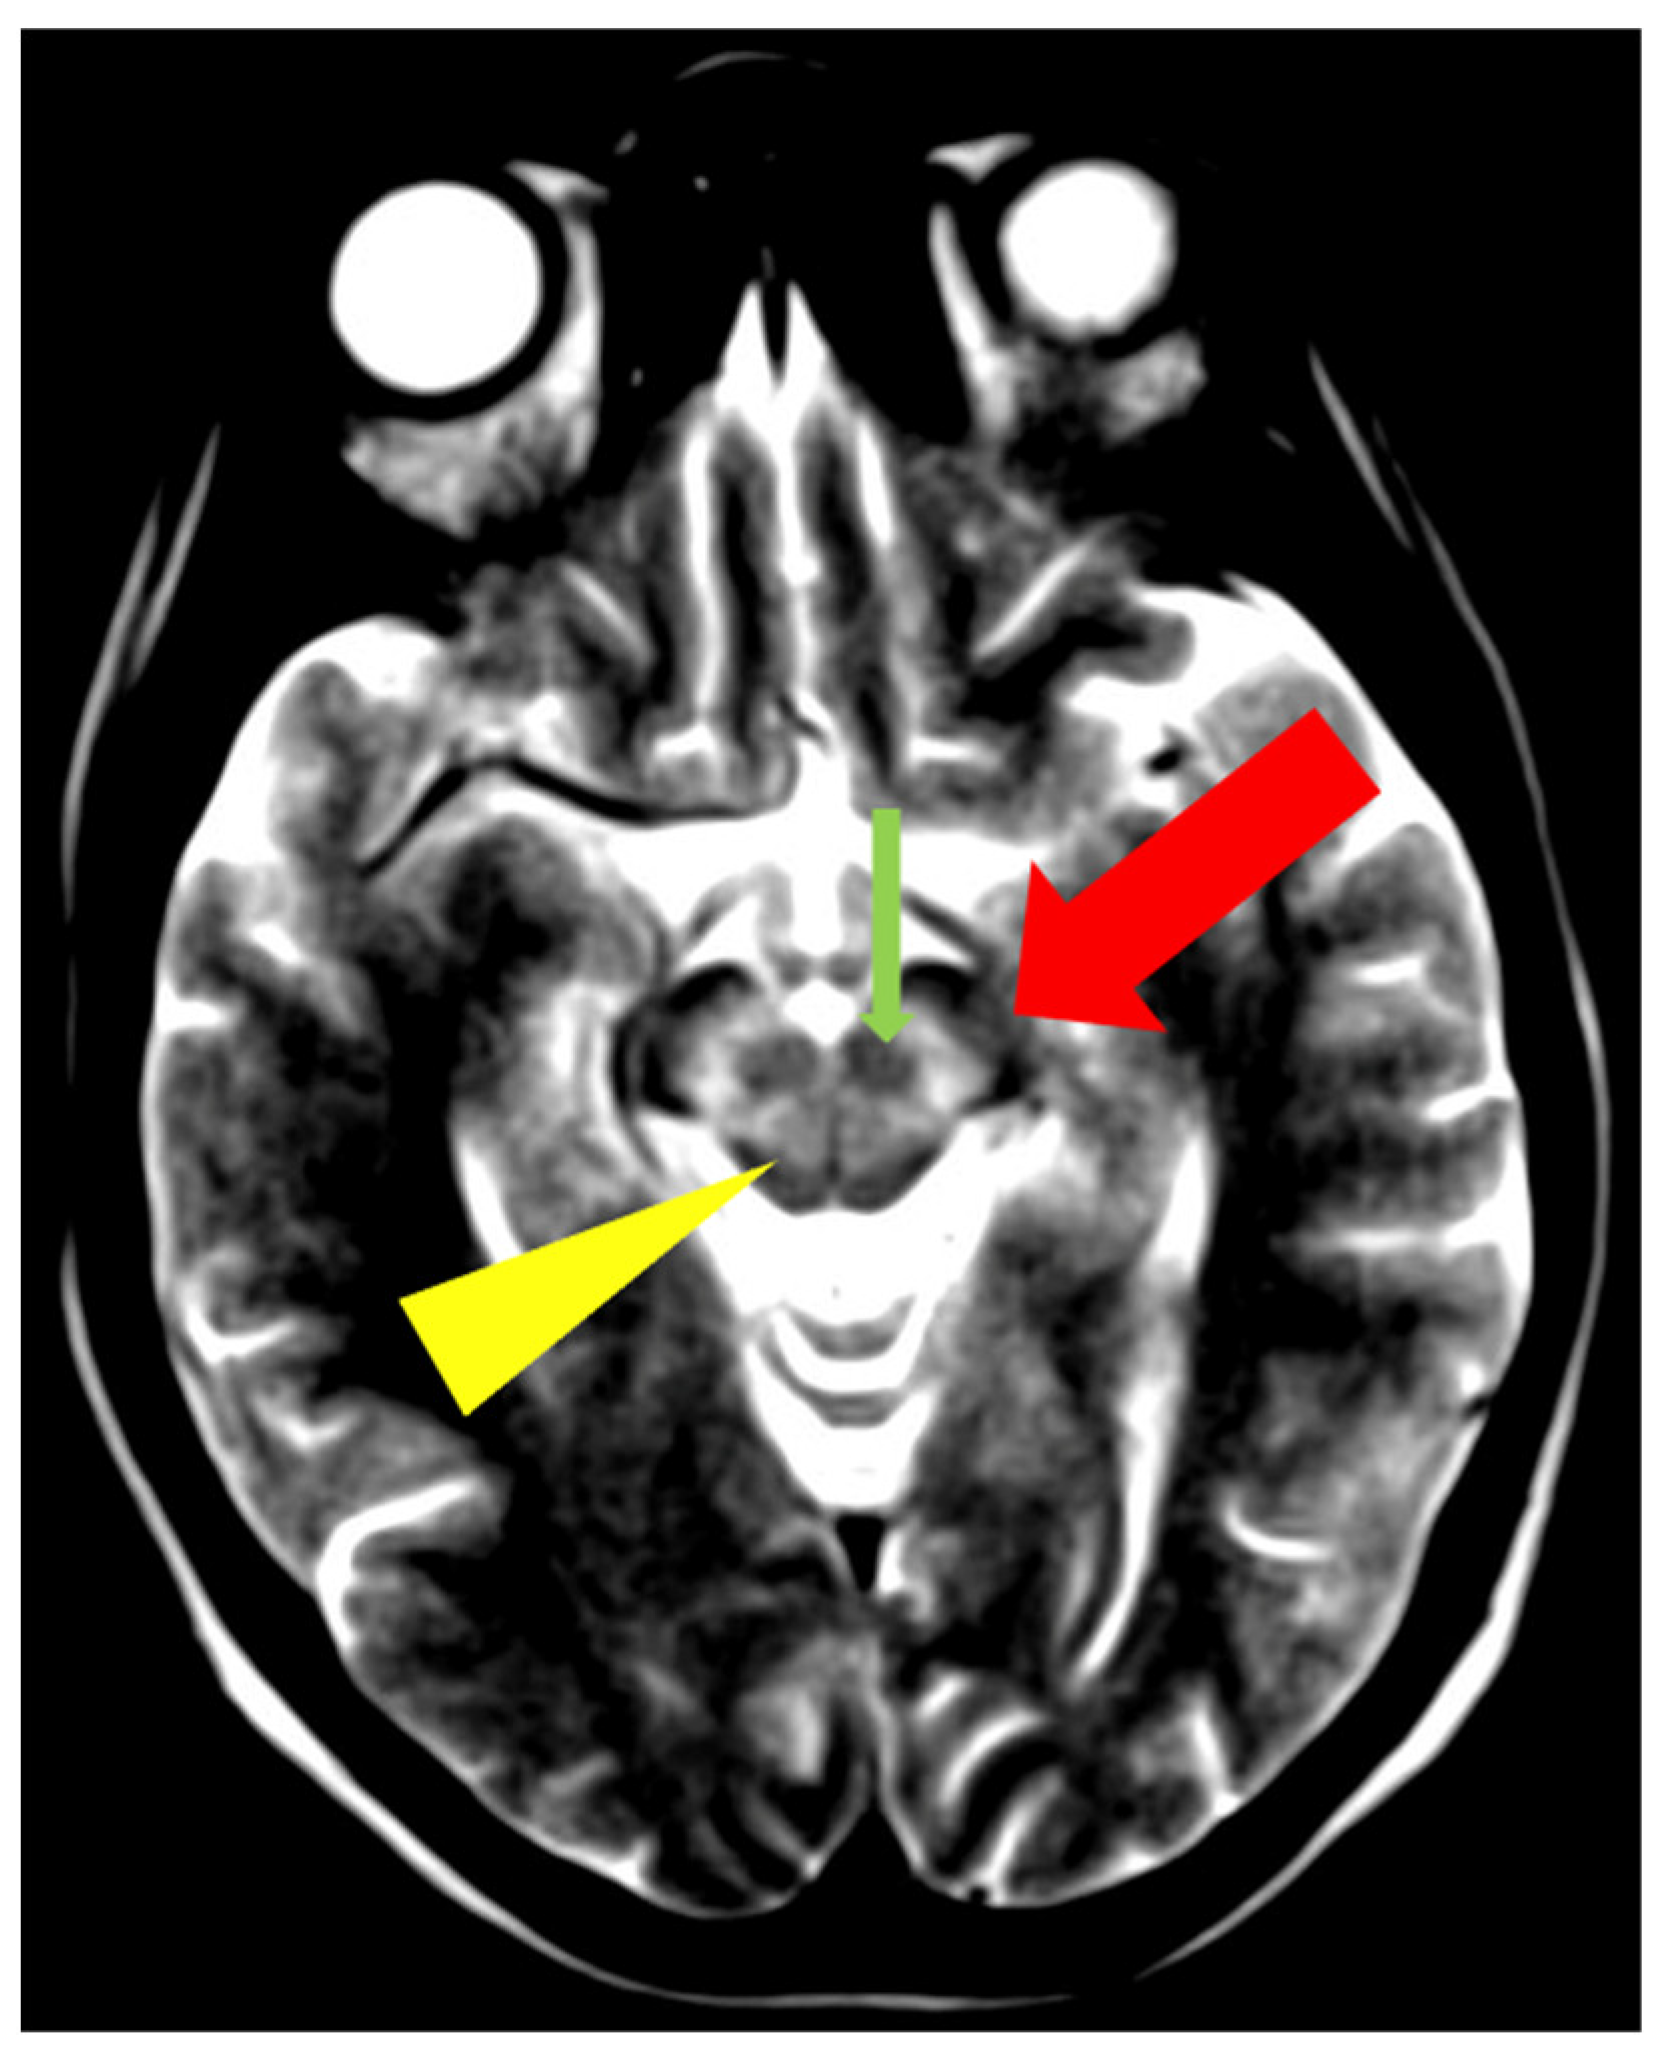

5. Neuroradiological Pathognomonic Signs of WD

- Hitoshi, S.; Iwata, M.; Yoshikawa, K. Mid-brain pathology of Wilson’s disease: MRI analysis of three cases. J. Neurol. Neurosurg. Psychiatry 1991, 54, 624–626. [Google Scholar] [CrossRef] [PubMed]

- George, U.; Varte, N.; Rathore, S.; Jain, V.; Goyal, S. “Split thalamus”: Internal medullary involvement in Wilson’s disease. Neurol. India 2010, 58, 680. [Google Scholar] [CrossRef] [PubMed]

- Sener, R.N. The claustrum on MRI: Normal anatomy, and the bright claustrum as a new sign in Wilson’s disease. Pediatr. Radiol. 1993, 23, 594–596. [Google Scholar] [CrossRef] [PubMed]